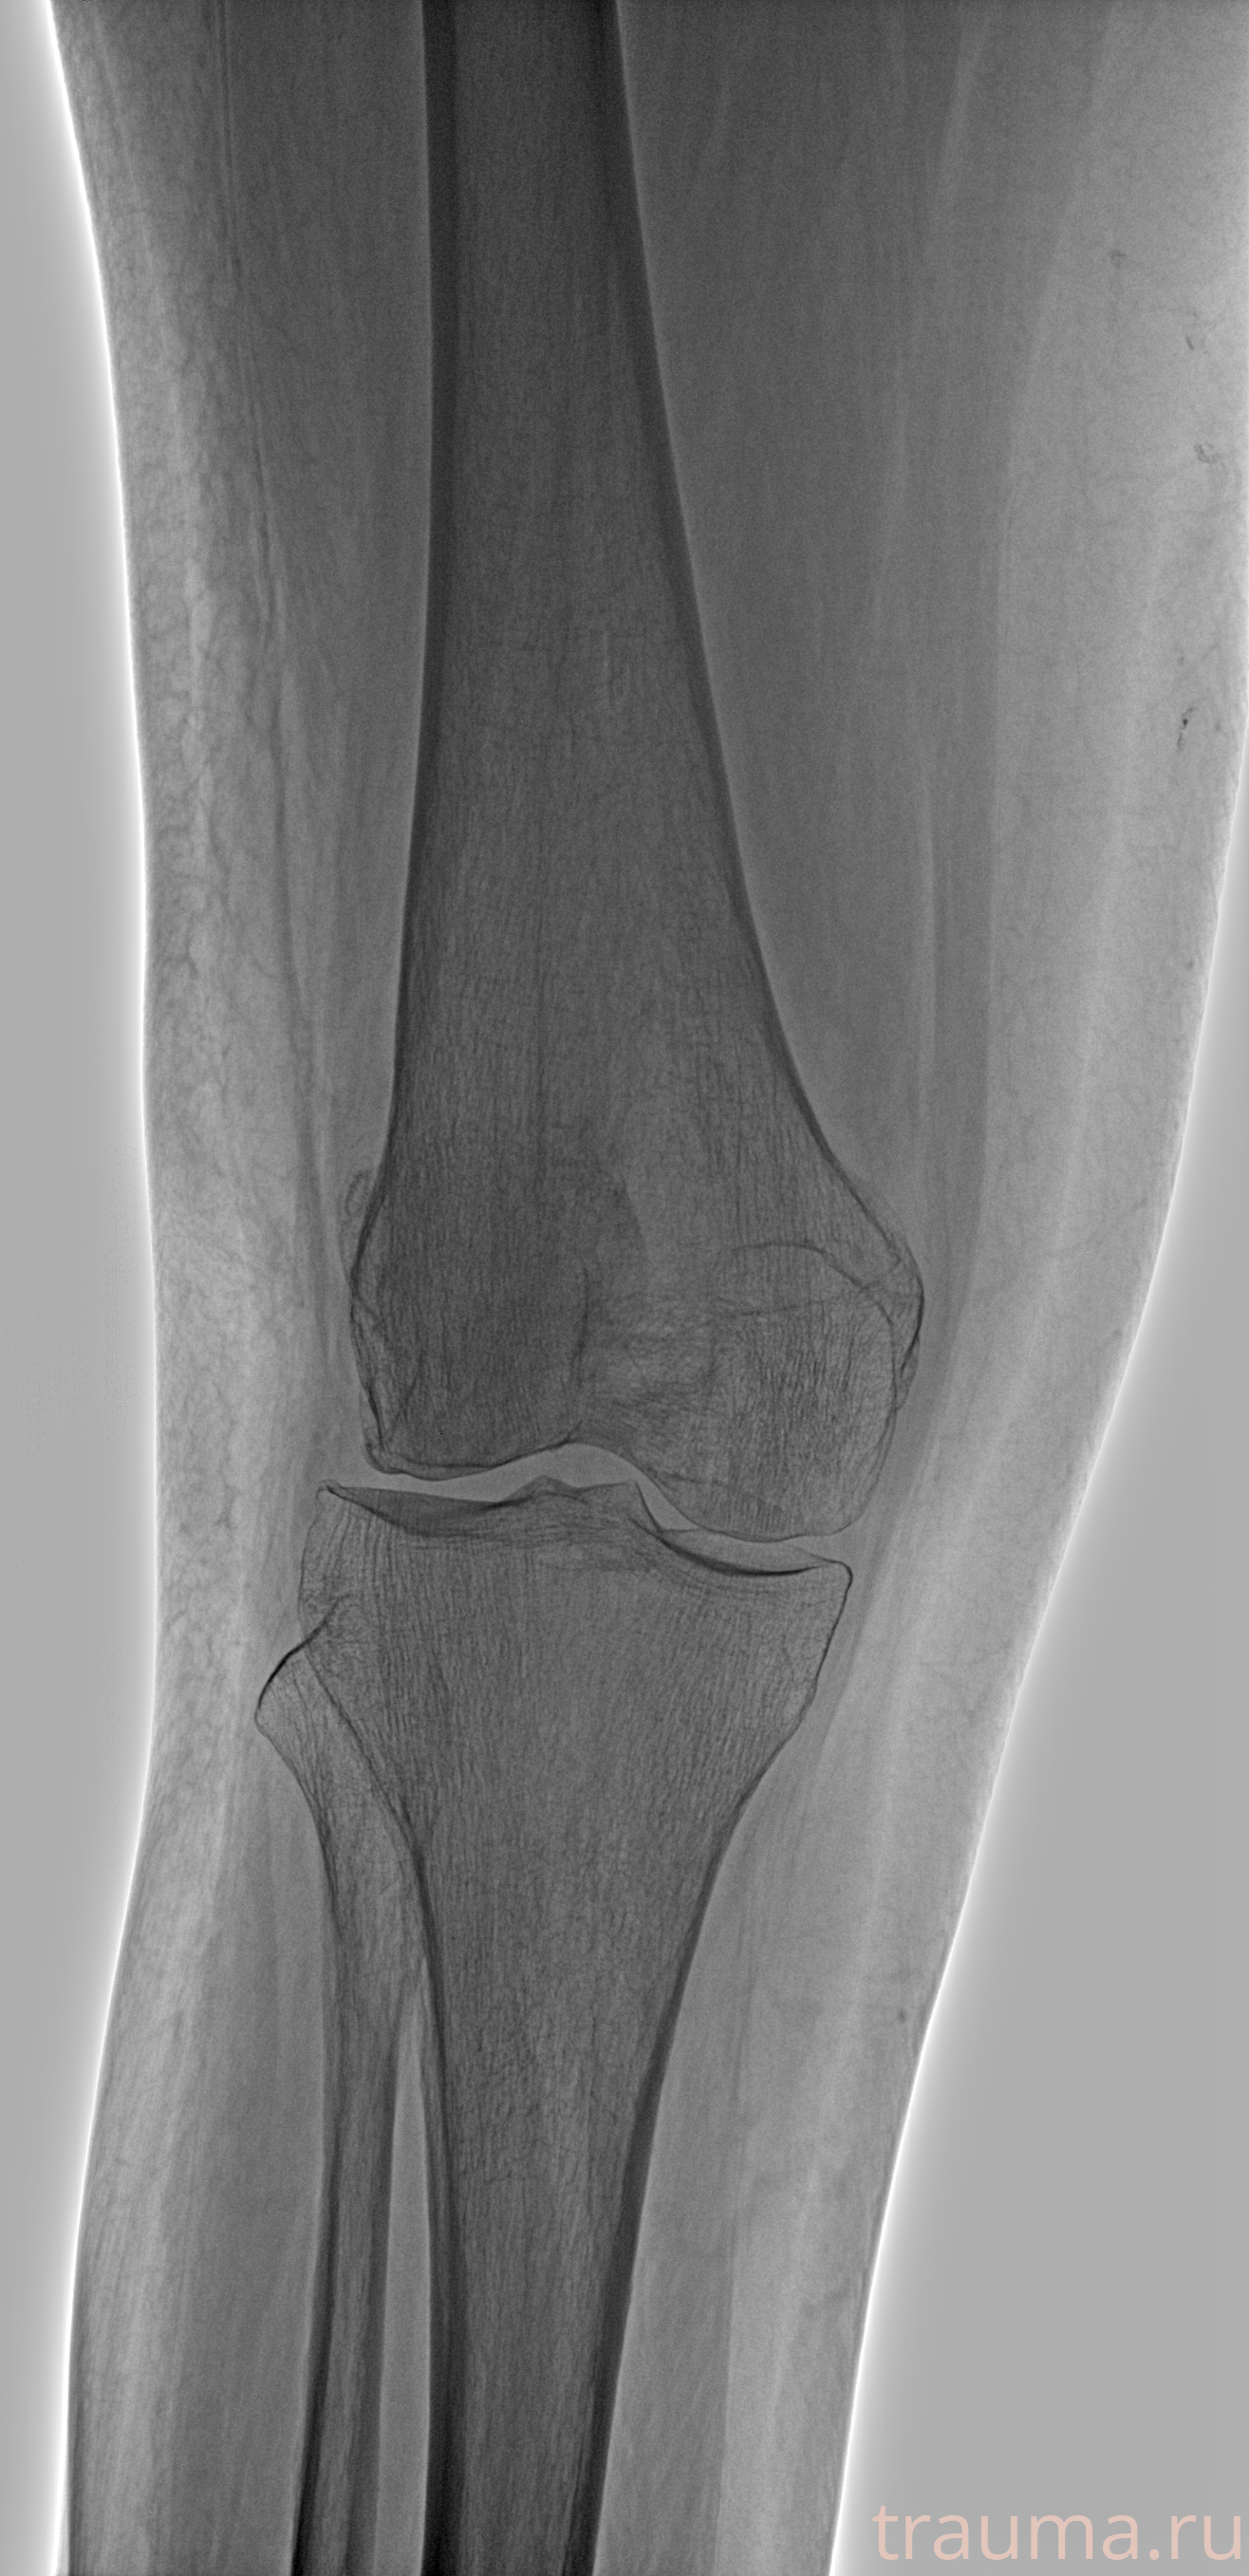

Рентгенограммы